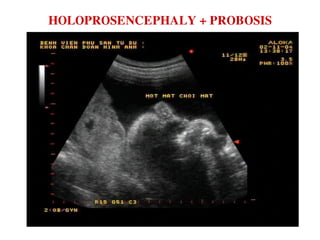

HOLOPROSENCEPHALY + PROBOSIS